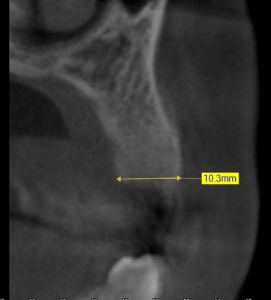

This video demonstrates alveolar ridge preservation following atraumatic surgical extraction of an endodontically treated tooth. Emphasis is placed on minimizing surgical trauma to preserve existing hard and soft tissues.

The case features flap management in the presence of a buccal dehiscence, followed by bone graft placement and stabilization using a dense polytetrafluoroethylene (d-PTFE) membrane. Surgical principles, membrane selection, and handling techniques are discussed to optimize ridge dimensions and facilitate future implant placement.